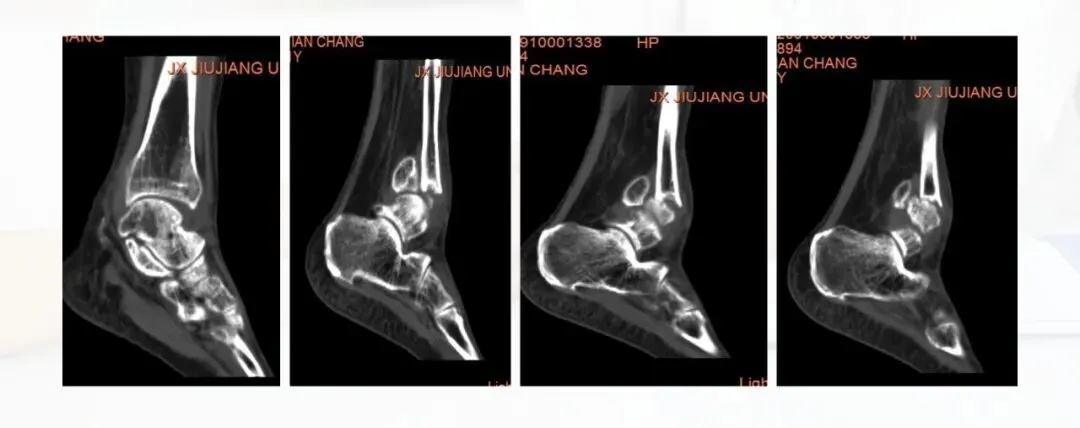

当前位置:首页>PPT>PPT纯享:陈旧性踝关节骨折的治疗案例(内附文献推荐)

PPT纯享:陈旧性踝关节骨折的治疗案例(内附文献推荐)